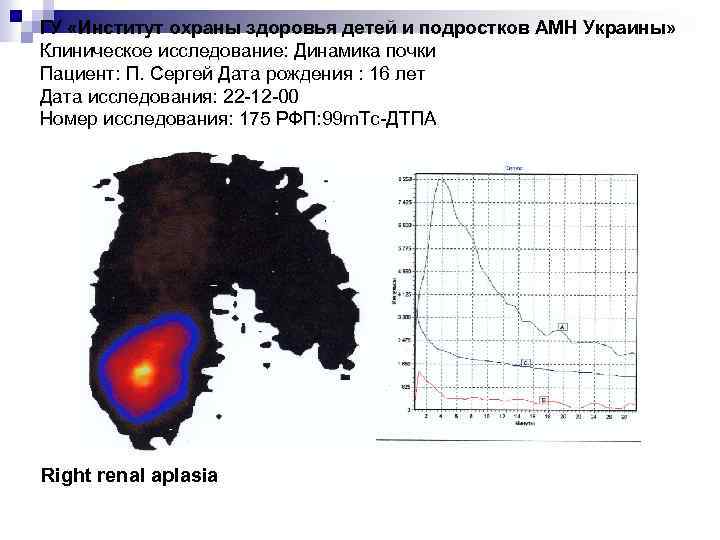

ГУ «Институт охраны здоровья детей и подростков АМН Украины» Клиническое исследование: Динамика почки Пациент: П. Сергей Дата рождения : 16 лет Дата исследования: 22 -12 -00 Номер исследования: 175 РФП: 99 m. Тс-ДТПА Right renal aplasia

ГУ «Институт охраны здоровья детей и подростков АМН Украины» Клиническое исследование: Динамика почки Пациент: П. Сергей Дата рождения : 16 лет Дата исследования: 22 -12 -00 Номер исследования: 175 РФП: 99 m. Тс-ДТПА Right renal aplasia